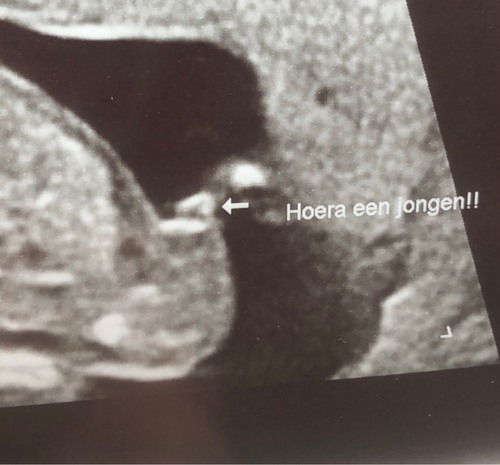

Bij een echte geslachtsecho zou ik wel een pottyshot foto verwachten. Vind dit plaatje niet heel duidelijk eigenlijk.

Oke als de bolling waar het pijltje naar wijst bij de nub hoord is het een jongen ja. Maar als het bij de navelstreng hoord dan wijst de nub op meisje. Het probleem is ook dat wat op de blaas lijkt niet een duidelijke jongenspositie heeft. Het zit precies op de rand dat het echt alleen aan de nub/geslacht te zien kan zijn.

Dit is heel duidelijk een jongen en absoluut geen navelstreng.

Bij mij gaven ze met de geslachtsbepaling echt wel garantie. Ik geloof niet dat ze het geslacht zouden zeggen als ze twijfelen, dan hadden ze je terug laten komen. Ik denk dus dat je gewoon kan vertrouwen op dat het een jongen is! Verloskundige is voorzichtig, die zei bij mij ook dat 14 weken wel erg vroeg is voor geslachtsbepaling.

Ah oke! Nou wellicht had zij het wel duidelijk gezien maar is de foto een beetje vaag en lijkt het hier op een navelstreng.

Hier nog een foto trouwens van diezelfde geslachtsbepaling, maar niet veel duidelijker?